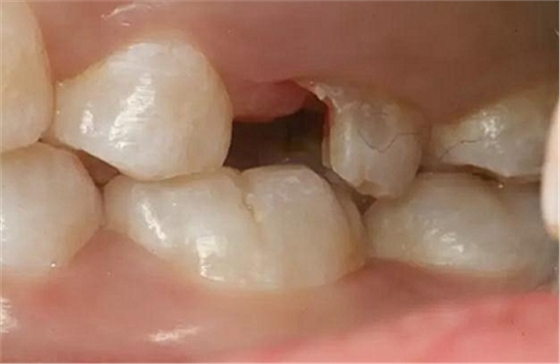

患者男性,35歲,B6銀汞充填后食物嵌塞,要求重新充填,口內(nèi)檢查見B6近中鄰頜面銀汞充填物,局部缺損,有繼發(fā)齲,去除原充填物及繼發(fā)齲,發(fā)現(xiàn)齲壞位于牙齦下方,給予冠延長手術(shù),同期嵌體預(yù)備,后一次性取模。(同樣設(shè)計(jì)為齦上邊緣)

硅橡膠取模后,灌注模型,科爾琥珀樹脂制作嵌體。

一周后拆線,口內(nèi)試戴合適,粘結(jié)嵌體。